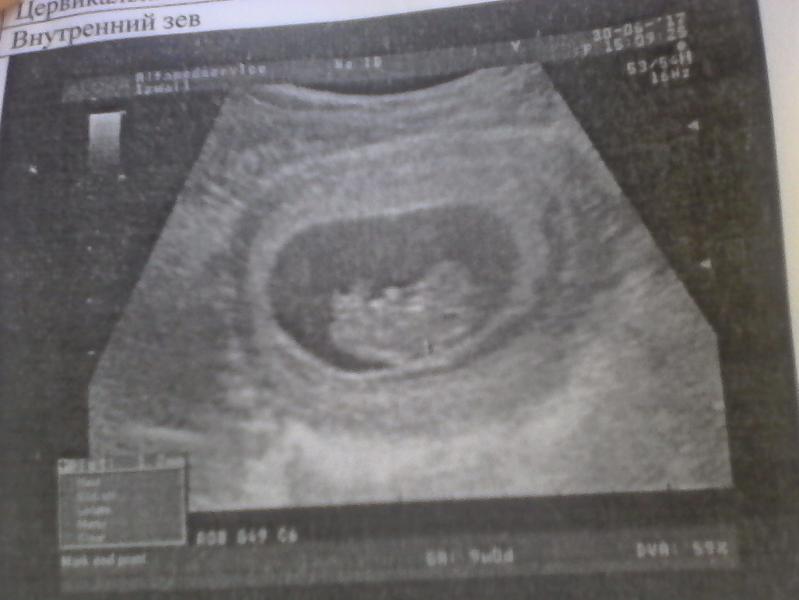

Мамулички- роднулички г. Измаил, подскажите кто делал на Кишинёва УЗИ можно ли снять на видео процесс, разрешают ли и сколько стоит?????😘😘😘😘😘

Не знаю как у вас, у нас в городе можно но заранее при записи об этом нужно сказать, и нужна новая флешка обязательно запакована.

Не так немного прочитала)) видео самого УЗИ можно записать на флешку